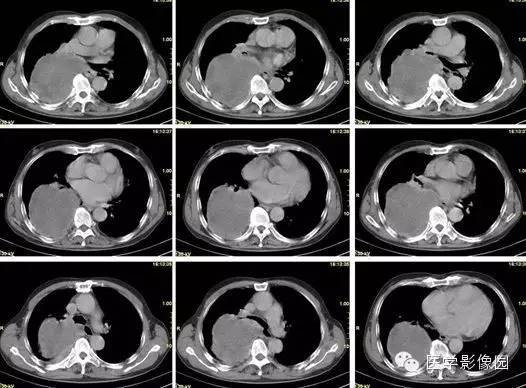

【病例】巨大中央型肺癌1例